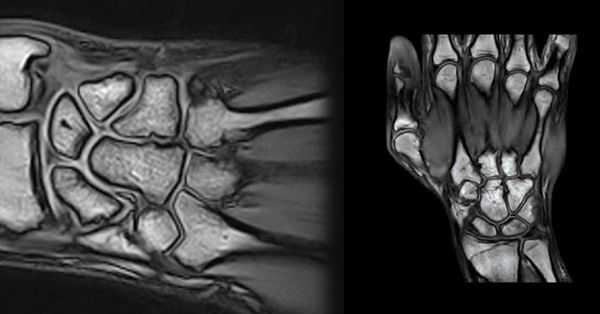

МРТ кисти, как и МРТ других суставов, применяется для выявления различных повреждений, прежде всего связочного аппарата, костных переломов (в дополнение к рентгенографии) и оценки состояния суставов. В лучезапястном суставе оценивается конгруэнтность и наличие жидкости.

На рентгенограммах хорошо видны дистальные переломы лучевой кости. Проблема диагностики возникает когда нет костных повреждений, но есть нестабильность. Ее можно определить на рентгенограммах по косвенным признакам - нарушению характерной линии вдоль соединения костей и увеличению расстояния между некоторыми из них. Однако только МРТ дает возможность увидеть разрывы связок, приводящие к нарушению конфигурации в запястье.

Из связок при МРТ кисти, прежде всего, оценке подлежит ладьевидно-полулунная, полулунно-трехгранная и треугольный фиброзно-хрящевой комплекс. Дополнительное значение имеют внутренние связки запястья, которые сложным образом соединяют мелкие кости между собой, а также с лучевой костью. Толщина этих связок от 1 до 3 мм. Повреждение перечисленных связок, особенно, полное или частичное заднего компонента, приводит к нестабильности в суставе. Фиброзно-хрящевой комплекс состоит из треугольного фиброзно-хрящевого диска и нескольких коротких связок, соединяющих кости запястья между собой, а также проксимальные концы локтевой и лучевой костей.

МРТ кисти. Корональная Т1-взвешенная и Т2-взвешенная МРТ. Трабекулярный перелом лучевой кости без смещения.

МРТ кисти. Корональные Т1- и Т2-взвешенные МРТ. Повреждение задней группы связок.